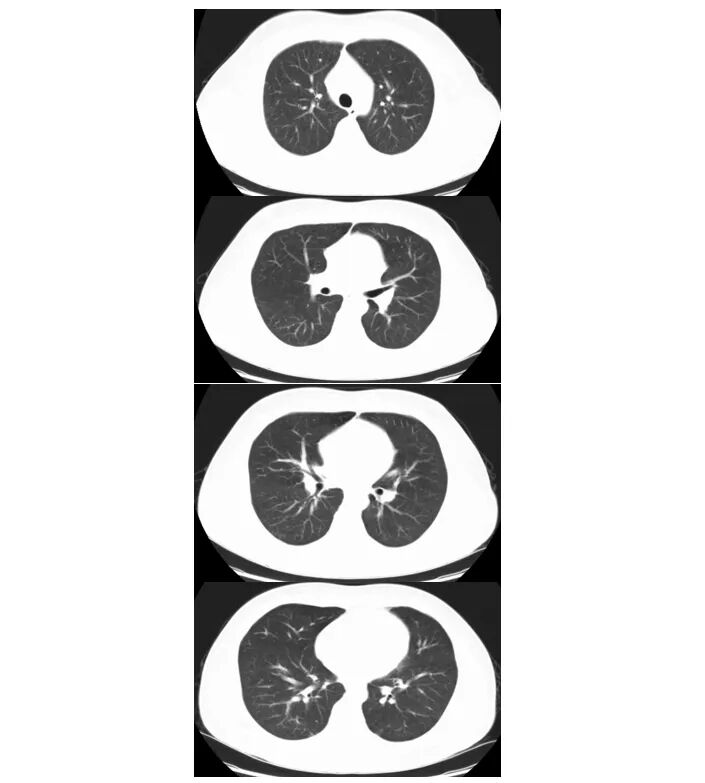

2025年1月15日体温平,皮疹好转,无咳嗽,指脉氧:99%。复查WBC 2.63×109/L,N 35.1%,L 1.36×109/L,EO 5.7%;CRP 2.21mg/L;ALT/AST 77/41U/L,1月15日胸部CT:1.双肺多发感染性病变已完全吸收消失。2.双肺下叶多发间质性改变未见显示。予出院,予比克恩丙诺片,更昔洛韦分散片,复方磺胺甲噁片口服,门诊随访。

2. 肺孢子菌肺炎:肺泡灌洗液tNGS两次均检出大量耶氏肺孢子菌序列(首次40564条;复查19354条),为确诊依据临床影像吻合:亚急性起病,进行性气促;胸部CT呈典型双肺弥漫性磨玻璃影;针对pjp的治疗(复方磺胺甲噁唑、克林霉素)后,临床症状及影像学明显好转。